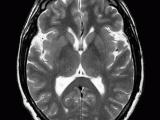

Gait troubles, incontinence, and dementia / wobbly, wet, & wacky Bob Fowler, the subject of this 60 minutes special, presented with this triad of symptoms and was ultimately diagnosed Alzheimer’s disease. He had been to doctor after doctor, and suffered with debilitating symptoms for nearly a decade including trouble walking, incontinence, and severe memory deficits … Continue reading

…The Brain That Is When visualizing the brain using a CT (computed tomography) there are some cute images that help you understand where in the brain you are looking: Totally looks just like it right ? (From my wonderful professor Dr. Linberg’s lectures, hover over pics for caption):